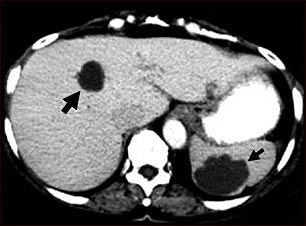

TC de quistes del hígado y el bazo

Esta TC abdominal muestra múltiples quistes en el hígado y el bazo. Se puede ver un quiste circular oscuro en el hígado (lado izquierdo de la pantalla) y un gran quiste circular irregular en el bazo (parte inferior derecha de la pantalla).